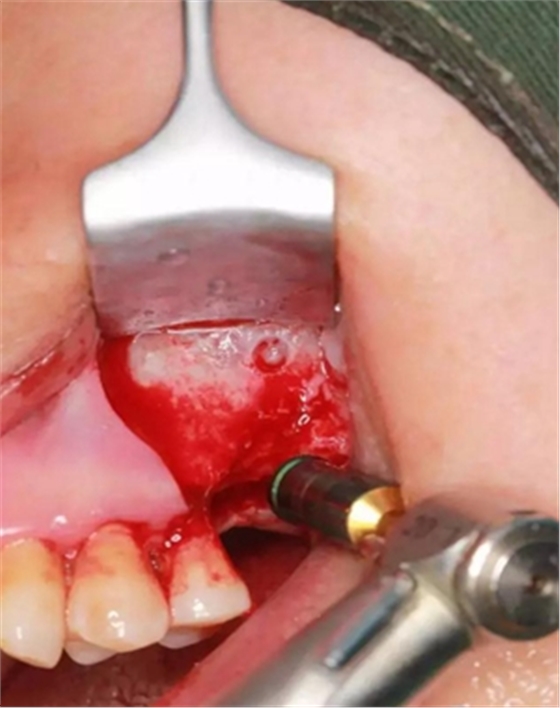

大家好,我是梁老師的助理小依。由于梁老師每天手術(shù)檔期安排較滿,加上經(jīng)常出差講課,沒有時間整理病例 。為了方便大家更及時的了解梁老師最新手術(shù)動態(tài),以后將由我為大家整理并推送梁老師最新經(jīng)典案例。案例文字旁白少,但圖片會盡量完整展示手術(shù)全過程,供大家學(xué)習(xí)參考。有任何問題,可以留言,梁老師會親自為大家解答。感謝大家對梁老師的支持和關(guān)注!